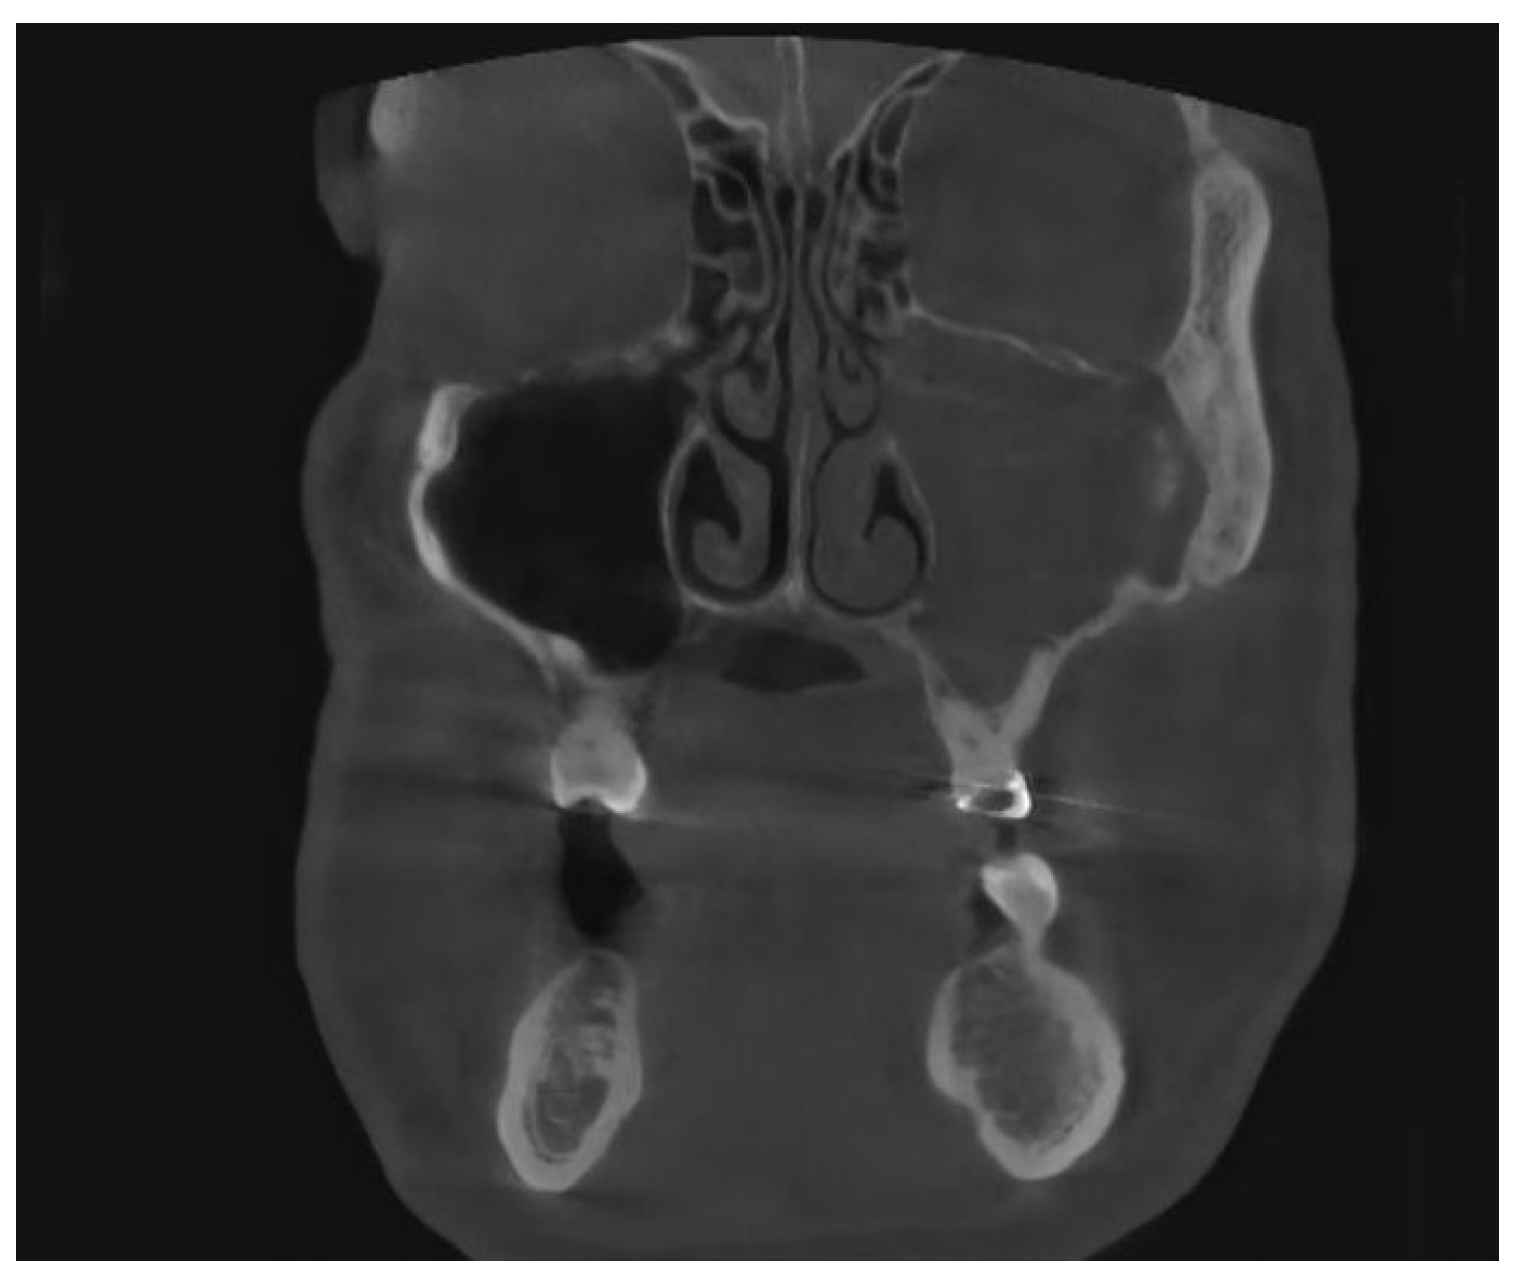

Figure 1 from Odontogenic Sinusitis is a Common Cause of Operative

Figure 1 from Etiologies and Treatments of Odontogenic Maxillary Odontogenic Sinusitis Diagnosis   based on multidisciplinary international consensus, diagnosing ods generally requires otolaryngologists to confirm.    — odontogenic maxillary sinusitis (oms) is a subtype of maxillary sinusitis (ms). It is actually inflammation of the.    — odontogenic sinusitis is a unique form of sinus disease requiring diagnostic and therapeutic approaches.  the particularity of an odontogenic maxillary sinusitis diagnosis is defined by. Odontogenic Sinusitis Diagnosis.

Odontogenic maxillary sinusitis Image Odontogenic Sinusitis Diagnosis   based on multidisciplinary international consensus, diagnosing ods generally requires otolaryngologists to confirm.  odontogenic sinusitis has distinct pathophysiology, diagnostic considerations, microbiology, and treatment strategies.    — odontogenic maxillary sinusitis (oms) is a subtype of maxillary sinusitis (ms). It is actually inflammation of the.    — current diagnostic criteria for odontogenic sinusitis are extremely heterogeneous.  the particularity of an. Odontogenic Sinusitis Diagnosis.